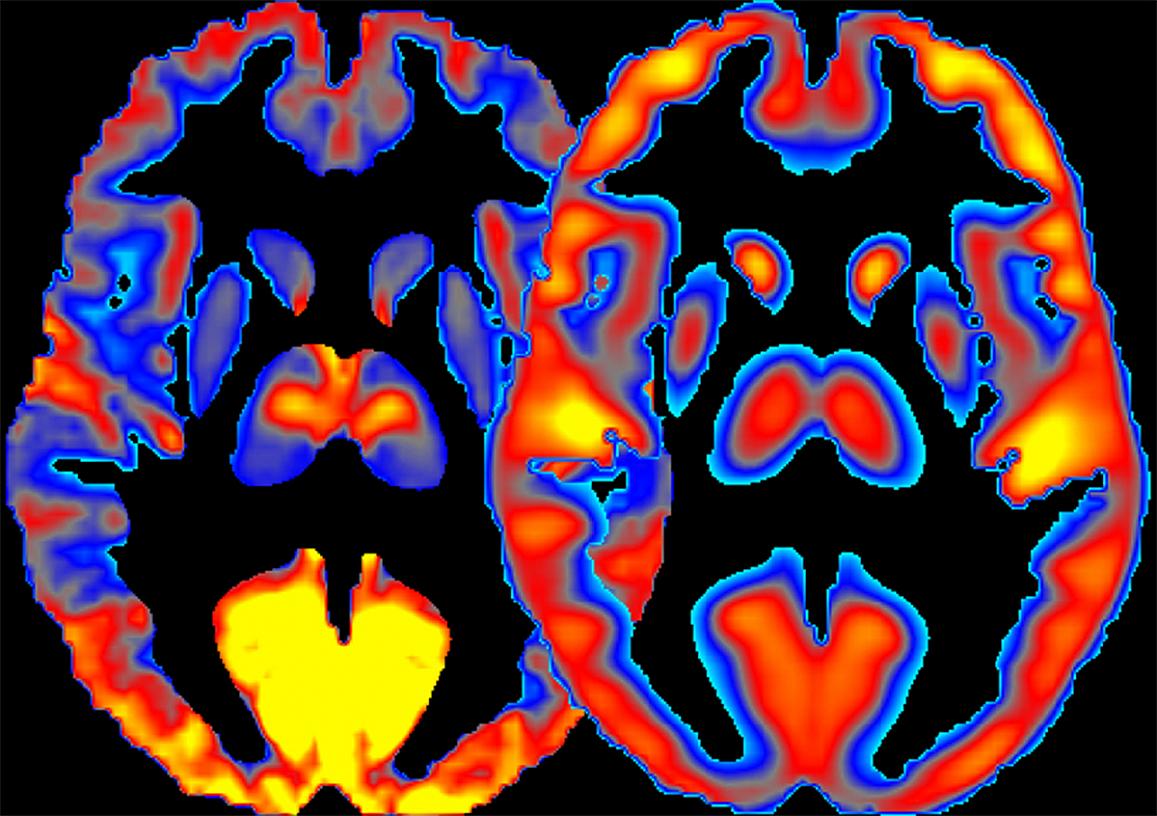

A new brain imaging study reveals that how people expect pain relief—through visual cues or treatment explanations—can significantly influence how much pain they actually feel. External cues, like symbols signaling less pain, consistently reduced pain perception and altered brain regions tied to pain processing.